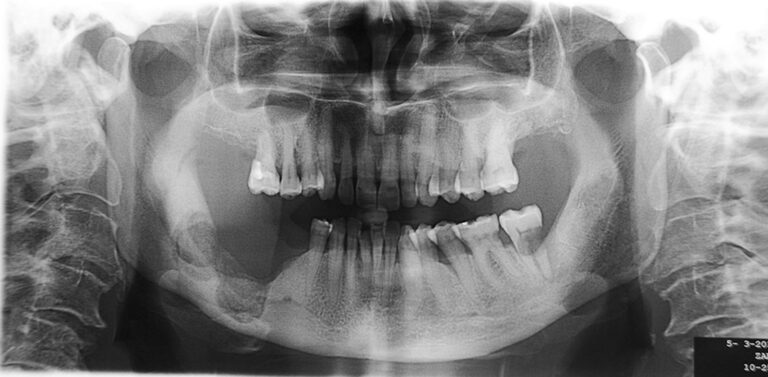

Le faccette dentali sono una soluzione estetica (lamine sottili posizionate nella parete esterna del dente) con diverse indicazioni: ad esempio discromie, abrasioni e anomalie della forma dei denti. La buona riuscita e la durata nel tempo sono legate alla condizione degli…